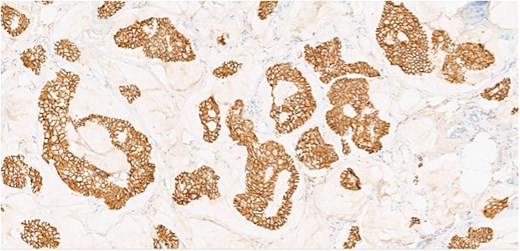

Herein, we present a 75-year-old man who, having been referred to our service with an inguinal hernia, raised concern about a palpable mass present in his right axilla. The main differential on initial examination was that of a simple epidermoid cyst, and consent was obtained for its removal during his elective hernia repair. Subsequent histology however, revealed a well differentiated MAC. There was extensive involvement of the deep and superficial reticular dermis (Figs 1and 2). Lymphovascular invasion was present. Sweat glands were focally involved by the carcinoma. The differential diagnosis included PCMC and metastasis from other primary sites of MAC such as breast, lung and gastrointestinal. Immunohistochemical profiling was performed on the specimen. CK 7, HER2 (4B5, 3+), GATA3 (strong, diffuse), and P16 (focal, weak) were positive (Figs 3–6). SOX10, CK 20, CDX2, TTF-1, p40, ER, and PR were negative which supported the diagnosis of MAC with either breast or PCMC origin based particularly on GATA3 expression.